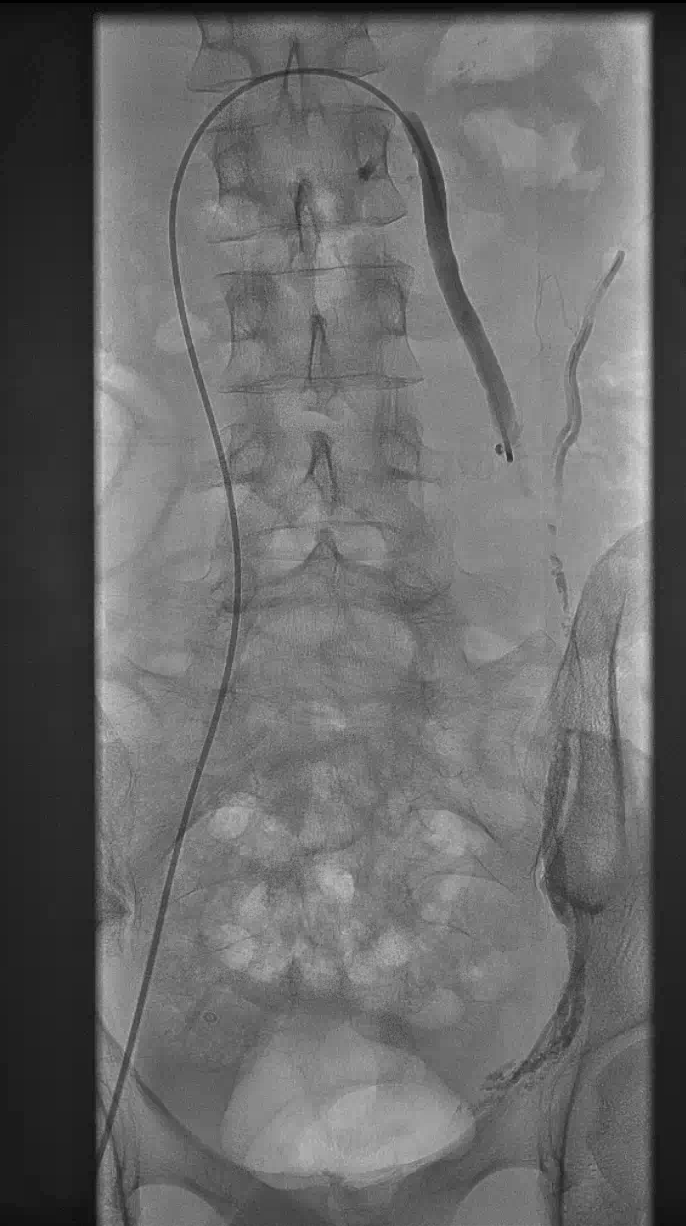

During the Procedure:

Local anaesthetic administration, sometimes with sedation

Small catheter insertion via arm, groin or neck

Real-time imaging guidance

Precise coil or glue placement

Procedure takes 30-60 minutes